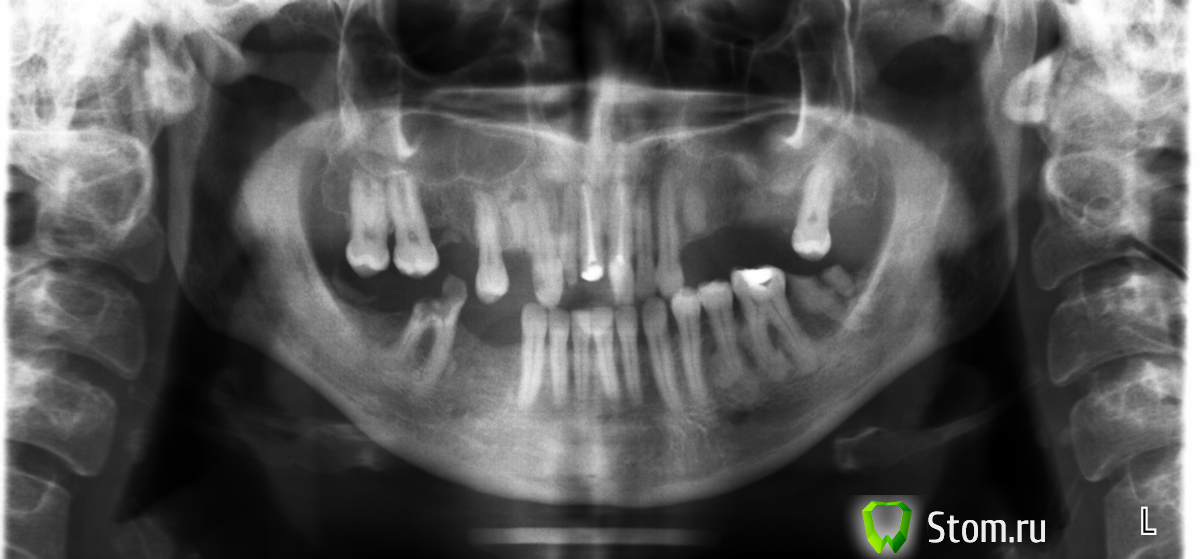

Ina Опубликовано 3 марта, 2012 Поделиться Опубликовано 3 марта, 2012 Здравствуйте! Подскажите, пожалуйста, хорошую клинику, где можно вылечить и удалить сразу несколько зубов под общей анестезией. Снимок прилагается. Я живу в городе Ижевске, но это не столь важно. Меня волнует не только лечение-удаление, но и протезирование, так как уже сейчас у меня мало осталось зубов, и среди них нет ни одного здорового.И еще. Раз в полгода мне приходиться проходить курс антибиотиков из-за удручающего состояния зубов. Хотелось бы обследоваться на распространение инфекции выше корней в кости, на наличие гноя в полостях головы и прочие сопутствующие неприятности.Спасибо.С уважением. Ина. Ссылка на комментарий